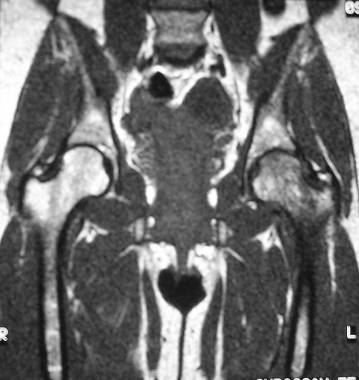

Transient osteoporosis